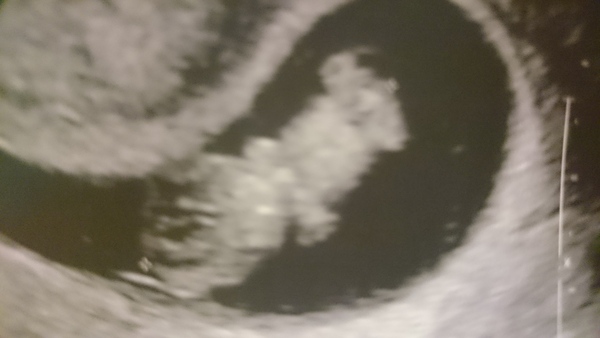

Here's a photo of my baby! He/she is waving to say hello to you all!

Wow! dont you love it when a baby looks like a baby in an early scan pic instead of a blob with a heartbeat! Loving the little arms and legs. Smile

Emma fab scan pic, u can really see its little arms waving!

Emma, that is such a cute scan picture.

Emma - SO pleased your scan went well. Amazing what they can see when they are so tiny! I saw a heart beating and the entire size of the baby is just 1.8cm so the heart must be about 1mm. Still amazed! Cute pic!!

Thanks emma your baby pic is beautiful!!